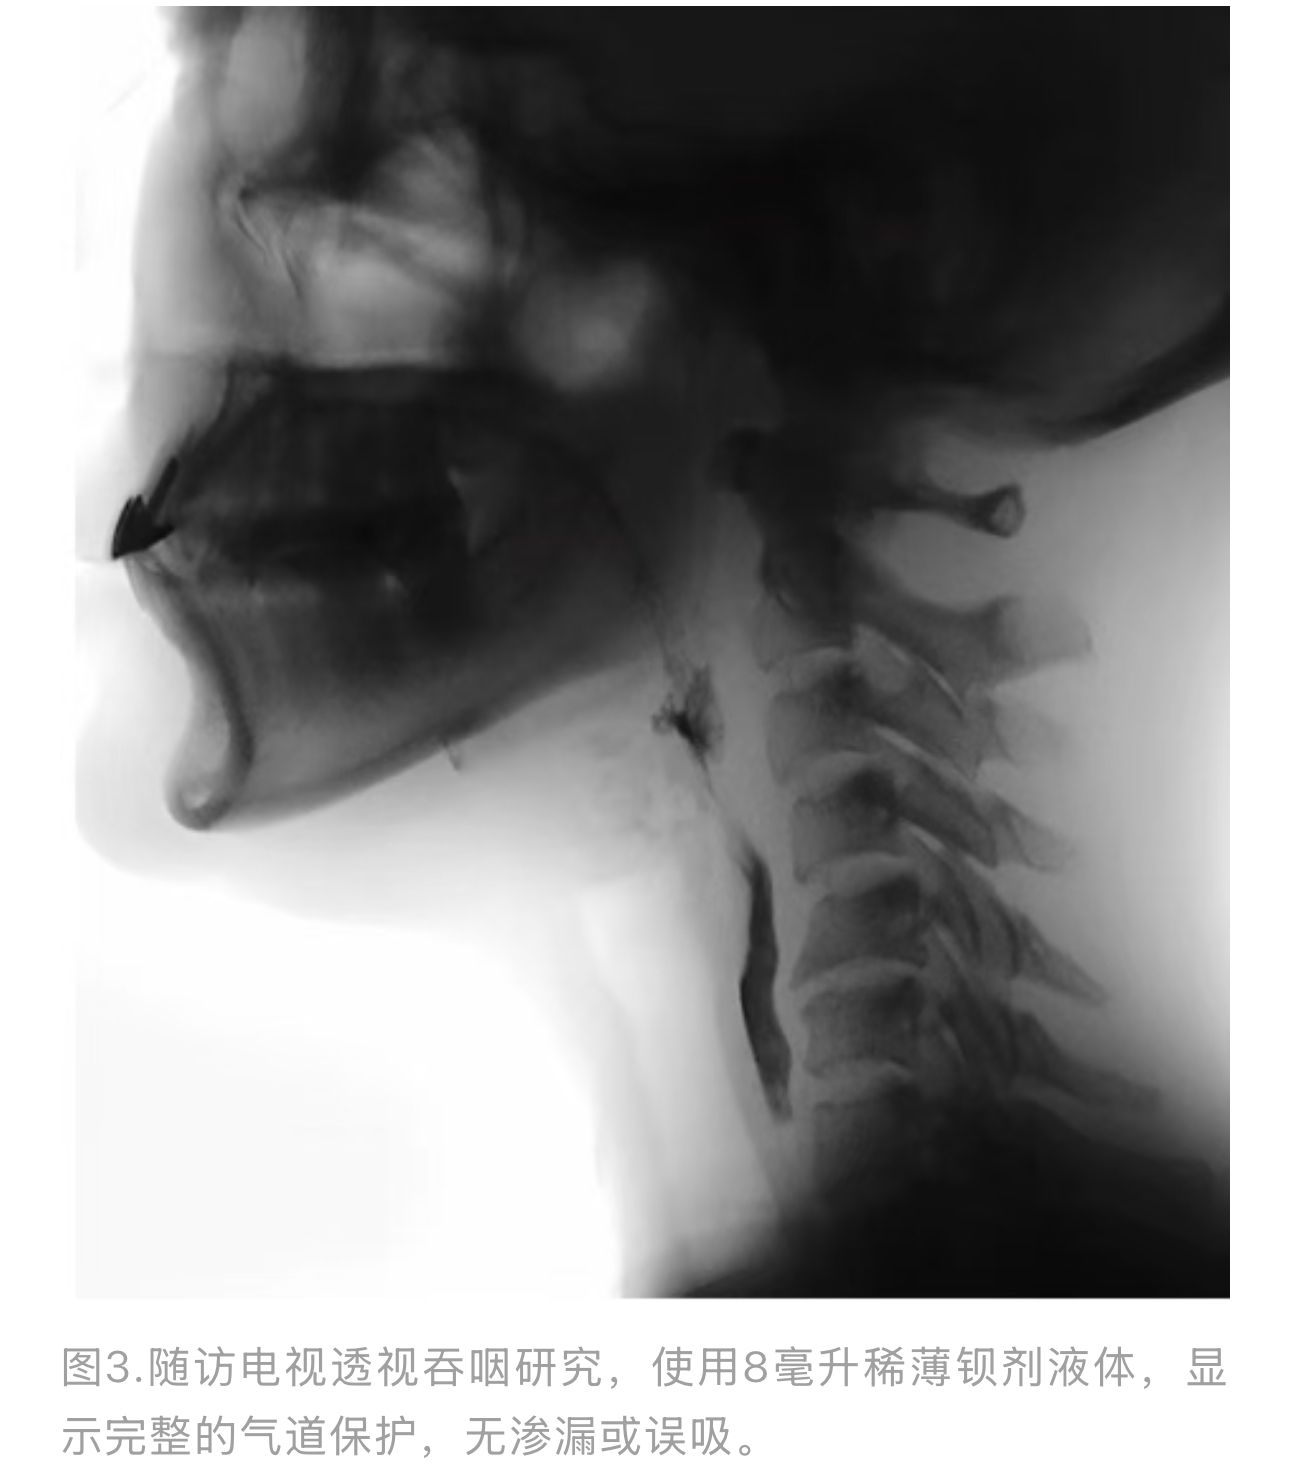

在肉毒毒素注射后约12周,进行了重复VFSS以客观评估其进展。该研究显示,与首次VFSS相比,吞咽功能显著改善(表2)。咽部传输时间恢复正常,所有性状食团的吞咽反射触发不再有明显延迟。吞咽时的软腭抬升和喉部抬升改善,导致有效的气道保护。研究期间未观察到误吸。半固体和固体食团无渗漏;即使是稀薄液体,几乎所有试验都能安全吞咽。仅有一次,在快速吞咽8毫升稀薄钡剂时观察到微量渗漏,少量造影剂短暂进入喉前庭但立即被排出,未下降至声带下方(PAS2)。患者能够通过自发的第二次吞咽清除任何轻度残留,会厌谷或梨状隐窝基本无显著残留。这些发现表明其吞咽机制接近完全恢复。她报告此时已恢复正常饮食,尽管对非常稀薄的液体仍保持谨慎(更倾向于小口啜饮水)。其功能性经口进食改善至FOIS5,EAT-10评分降至8,反映出中度的残留症状但显著的临床改善。

肉毒毒素注射后5个月,患者报告其吞咽功能"恢复正常"。注射后5个月进行的第三次VFSS证实了近乎完全的恢复(表2)。即使连续吞咽未增稠液体,也未观察到渗漏或误吸(图3),所有性状的食物都能安全吞咽。无残留,所有代偿性策略均不再需要。她完全恢复了正常饮食和不受限制的液体摄入,对应FOIS7,其EAT-10评分为1,表明主观困难极小。夜间咳嗽